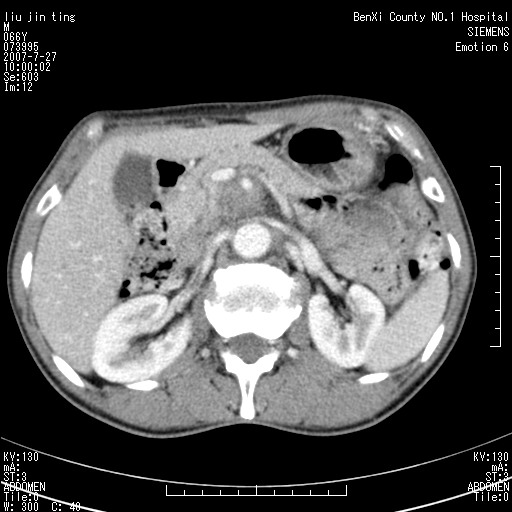

腹痛,背痛,无恶心呕吐,不黄,彩超示胰腺钩癌,ct扫描病灶平扫30-40hu,增强后动脉期40--60hu,静脉期50-68hu,真的是钩突上的么?您要试一试么?

静脉期

沿着肠系膜上动脉呈匍匐性生长的软组织肿块,形态不规则,包绕肠系膜上动脉,呈明显强化,考虑来源于肠系膜的恶性肿瘤

腹腔干至肠系膜上动脉水平肿大淋巴结影可能性大.

沿着肠系膜上动脉呈匍匐性生长的软组织肿块,形态不规则,包绕肠系膜上动脉,呈轻-中度强化,考虑来源于肠系膜的恶性肿瘤。

钩突是正常的,只见腹膜后淋巴结的肿大,考虑淋巴瘤或转移可能。

支持!恶性纤维组织细胞瘤可能,与淋巴瘤及淋巴结转移鉴别(腹主动脉周围清晰,其他部位亦未见明显肿大淋巴结)。

后腹膜肿块,包围血管,考虑淋巴恶性病变,淋巴瘤或转移。